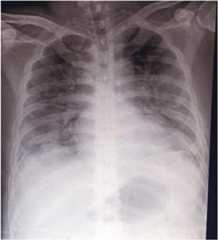

On admission to the ward on January 25 (illness day 5), patient 1 complained of a dry cough, but the sore throat had improved. She was awake and conversant with a blood pressure of 110/80, HR 84, RR 18 and temperature 36.8 °C. Her chest was clear. The remainder of the physical examination was unremarkable. Nasopharyngeal and oropharyngeal swab (NPS/ORS) specimens were collected and sent to the Research Institute for Tropical Medicine (RITM) in Muntinlupa City [5]. A chest radiograph was reported as unremarkable (Fig.3).

Fig. 3.

Posteroanterior chest radiograph of patient 1, 27 January 2020 (illness day 7). Unremarkable